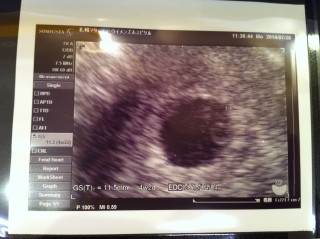

前回流産してしまってからの再び妊娠。 前回は育ちが遅かったけど、今回はよく育ってくれてるようです。 5w9dくらいかと思っていたら大きさでは4w2dくらいだと言われた。 あわよくば心拍確認も??なんて思ってたけどまだできず、2週間後に来てください、とのことでした。 2週間後が待ち遠しいです!! GSは12.1mmでした。

妊娠検査薬陽性から初めての病院。胎嚢と卵嚢黄が確認出来ました。胎嚢は16.1ミリで、お医者さんからは順調おめでとうと言っていただきました^_^ 38歳と高齢ですが、授かった大切な命を大事に大事に育てたいと思います。